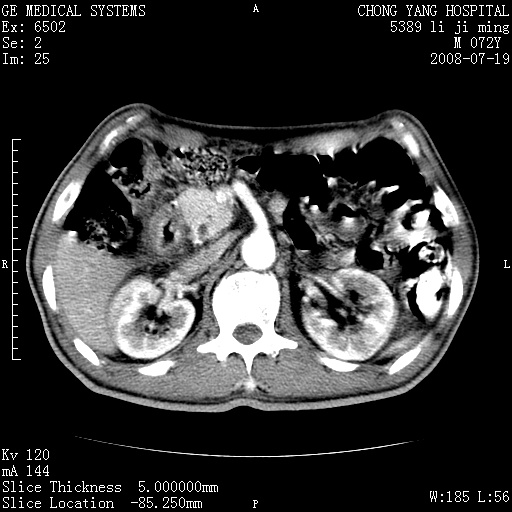

以下是引用zjzjr在2008-7-19 20:57:00的发言:[br]胰头增大,边缘模糊,周围可见渗出影,右侧肾前筋膜增厚.支持胰腺炎.

以下是引用yangyudong333在2008-7-20 6:56:00的发言:[br]胰腺增大尤以胰头明显,边缘模糊,周围可见渗出影,右侧肾前筋膜增厚,肠管於涨.支持胰腺炎

以下是引用不学无术在2008-7-19 23:15:00的发言:[br]胰腺增大尤以胰头明显,边缘模糊,周围可见渗出影,右侧肾前筋膜增厚,肠管於涨.支持胰腺炎